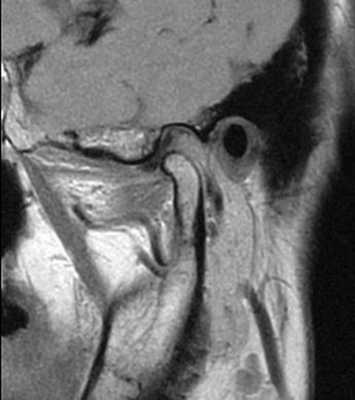

69-летняя пациентка с основными жалобами на боли в проекции челюсти, ограниченное открытие полости рта и невозможностью выдвинуть челюсть вперед обратилась за стоматологической помощью. Со слов пациентки ее симптомы начали развиваться около 6 месяцев назад: именно тогда она заметила, что ей трудно выдвигать челюсть вперед, чтобы посвистеть к своей собаки. По данным анамнеза на протяжении около 50 лет больная отмечала «выскакивание» и «пощелкивание» челюсти с левой стороны, и данные симптомы прекратились приблизительно в то время, когда ей стало трудно выдвигать нижнюю челюсть вперед. В ходе клинического осмотра было обнаружено, что максимальная величина межрезцового расстояния составляла 35 мм, при этом в ходе максимального открытия полости рта челюсть несколько смещалась влево. После массажа и растяжения левой жевательной мышцы и сустава снизилась интенсивность болевых ощущений, однако объем движений не увеличился. Таким образом был поставлен диагноз левостороннего смещения суставного диска без сопровождающейся редукции ВНЧС. Пациентка была направлена на магнитно-резонансную томографию (МРТ), и для исследования локализации и состояния диска при открытом и закрытом рте. Данные МРТ позволили установить, что с левой стороны отмечалось переднее смещение суставного диска в обеих положения, что также подтверждает диагноз смещения без редукции (фото 1-4).

Фото 3. МРТ-скан левого ВНЧС при закрытом состоянии рта: визуализация переднего смещения диска без редукции.

Фото 4. МРТ-скан левого ВНЧС при закрытом состоянии рта: визуализация переднего смещения диска без редукции.